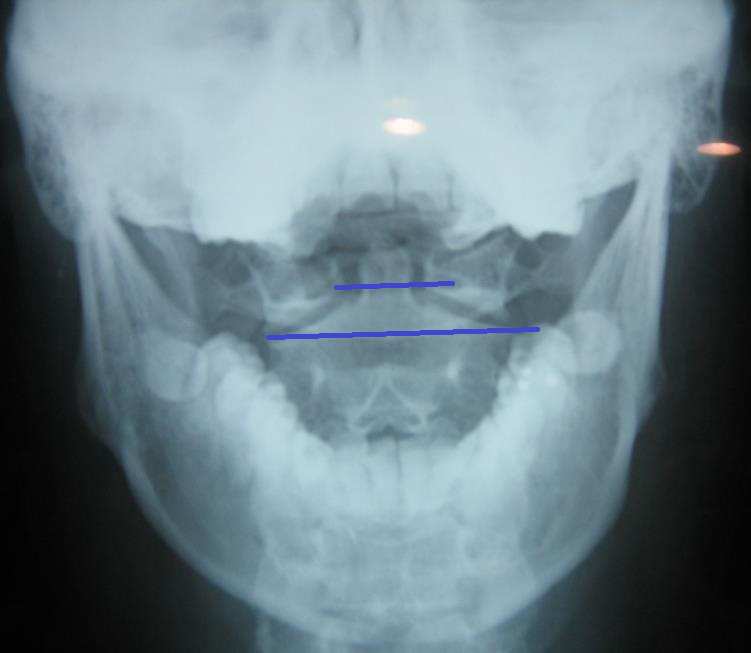

턱관절

• 첫째, 관절을 치료하는 수기요법 즉 추나요법은 관절이 묶여서 잘 움직여지지 않고 그와 연관된 신경계 증상을 나타내는 부위를 치료포인트로 잡고 이를 치료하는 것입니다. 그런데 턱관절은 이미 설명해 드린바 대로 대개 근육성이 많지 턱 관절 그 자체가 묶여서 안 움직이는 경우는 흔하지 않습니다.

• 둘째, 턱 관절의 근육을 긴장시키는 주된 원인이 턱관절 그 자체에 많은 경우는 내재적으로 치과적 문제를 가지고 있거나 관절상태 자체에 퇴행변화를 가져오는 경우를 제외하고는 대개 상부 경추의 이상으로 인한 2차적 긴장 형태가 주를 이룹니다. 따라서 상부 경추만 잘 치료해도 턱 관절의 긴장은 상당 부분 해소됩니다.

• 셋째, 관절은 원래의 가동성이 어느 것이 더 좋으냐를 따져봐야 하는데 턱 관절보다는 상부경추의 가동성이 훨씬 적기 때문에 관절이 묶일 때는 상부경추가 더 쉽게 묶이는데 반해 턱 관절은 기본적인 가동성이 매우 좋기 때문에 관절 자체가 묶이기는 쉽지 않습니다.